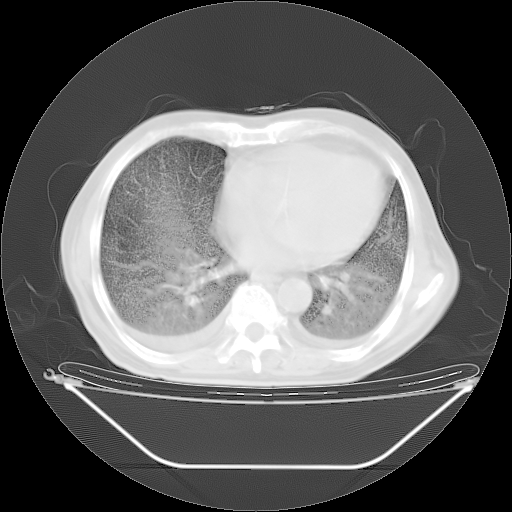

今天复查肺部CT,发现双肺广泛磨玻璃样改变。所以我把3月19日和5月9日相隔50天的肺部CT上传。请大家会诊。

5月9日肺部CT(在4月27日齐鲁医院肺部CT描述部分肺组织磨玻璃样改变,12天后肺组织广泛磨玻璃样改变)

2009年5月9日肺部CT

大致读了系列胸部CT:纵隔窗无明显异常,肺窗:从4、27至今:主要是双肺中下野外带可见毛玻璃样改变,目前处于急性肺泡炎阶段,至于原因考虑1、结替组织或胶原血管性疾病所致?2、恶性疾病如恶组在肺部所致的表现或细支气管肺泡癌?3、药物或其它原因如肺蛋白沉着症所致肺泡炎目前不太可能?总之,明天就去请我院的呼吸科、感染科、血液科和临免专家会诊哈。